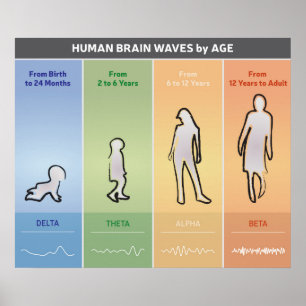

Diagrama das ondas do cérebro humano - Poster das

Preço38,10 €